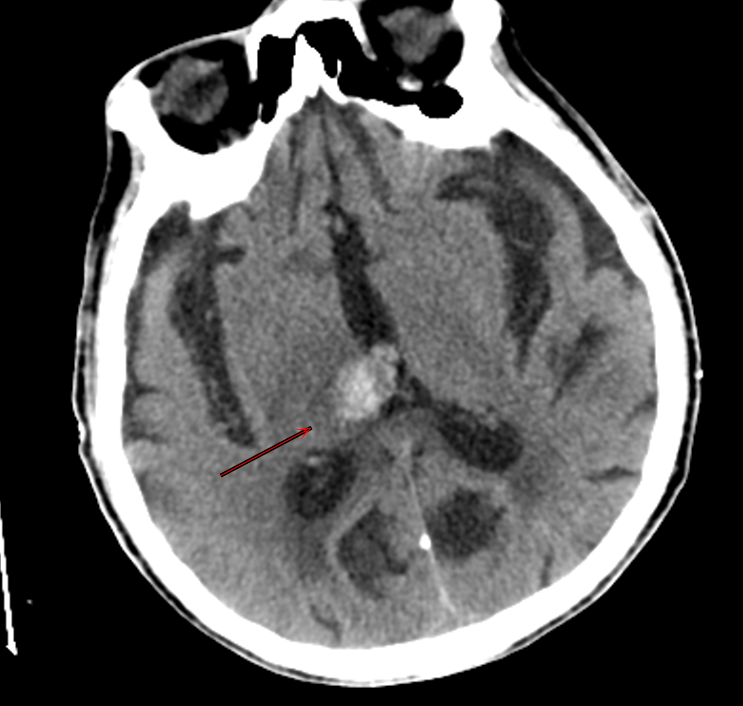

"患者意识不清,双侧瞳孔不等大!"接诊医生周淑清的呼喊打破了夜的宁静。急诊团队立即启动绿色通道,15分钟内完成头胸腹CT检查。

结果令人揪心:急性脑出血合并乙状结肠癌完全性肠梗阻,肠镜结果乙状结肠肠腔完全堵死。"就像两把刀同时架在脖子上。"患者的主治医师邵庆亮这样形容当时的危急情况。

脑出血急性期是乙状结肠癌手术的禁忌,但乙状结肠癌造成的肠梗阻不解决会随时危及患者的生命。普外六科主任张志强意识到病情的危急和复杂,立即召集科室医生讨论手术方案。经综合考虑及评估,大家一致表示,“做、必须做”,立即为其实施乙状结肠癌切除、乙状结肠单腔造瘘术,这个决定的背后,是不辜负"把急诊外科打造成生命最后防线"的嘱托,也是全体医生顶住压力、承担风险的担当。